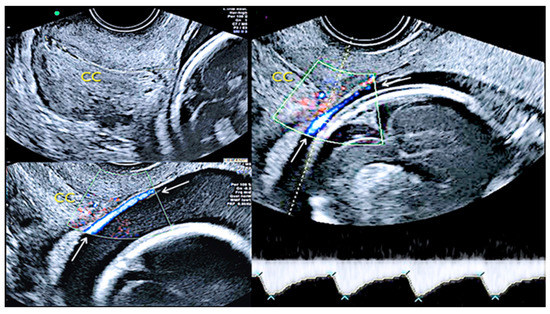

3.1.4. Circumvallate Placenta

- Arlicot, C.; Herve, P.; Simon, E.; Perrotin, F. Three-dimensional surface rendering of the chorionic placental plate: The “Tire” Sign for the diagnosis of a circumvallate placenta. J. Ultrasound Med. 2012, 31, 337–341. [Google Scholar] [CrossRef]